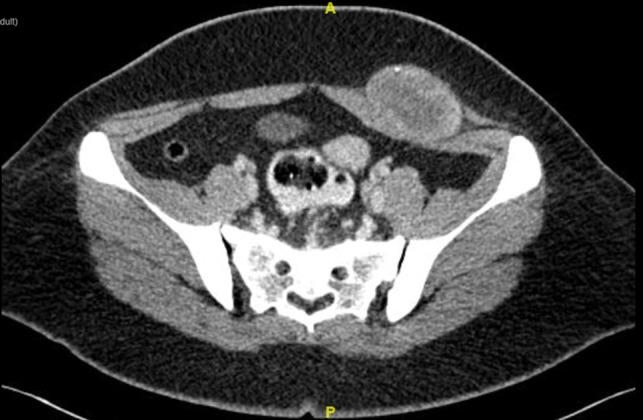

Natural history of abdominal wall soft tissue sarcoma is still poorly understood due to its rarity. In unpublished data of our institution, only seven cases of abdominal wall soft sarcoma with ICD-10 coding of 49.4 were found for past 10 years. We illustrate a case of juvenile fibrosarcoma of anterior abdominal wall. This is a case of young girl with anterior abdominal wall tumour, underwent wide local excision with immediate reconstruction. There are few options of surgical treatment for this case, but which is the best. It is always a challenge in managing young patient with giant abdominal wall defect in view of long term effect namely weakened abdominal wall, pregnancy related issue and risk of herniation and surgical site recurrence as well.

由于腹壁软组织肉瘤罕见,其自然病史仍未得到充分了解。在我们机构未发表的数据中,过去10年仅发现7例国际疾病分类第十版(ICD-10)编码为49.4的腹壁软组织肉瘤。我们展示了一例前腹壁青少年纤维肉瘤病例。这是一名患有前腹壁肿瘤的年轻女孩,接受了广泛局部切除并立即进行了重建。该病例的手术治疗选择有限,但哪种是最佳选择呢?鉴于长期影响,即腹壁薄弱、妊娠相关问题以及疝形成和手术部位复发的风险,对于患有巨大腹壁缺损的年轻患者进行管理始终是一项挑战。